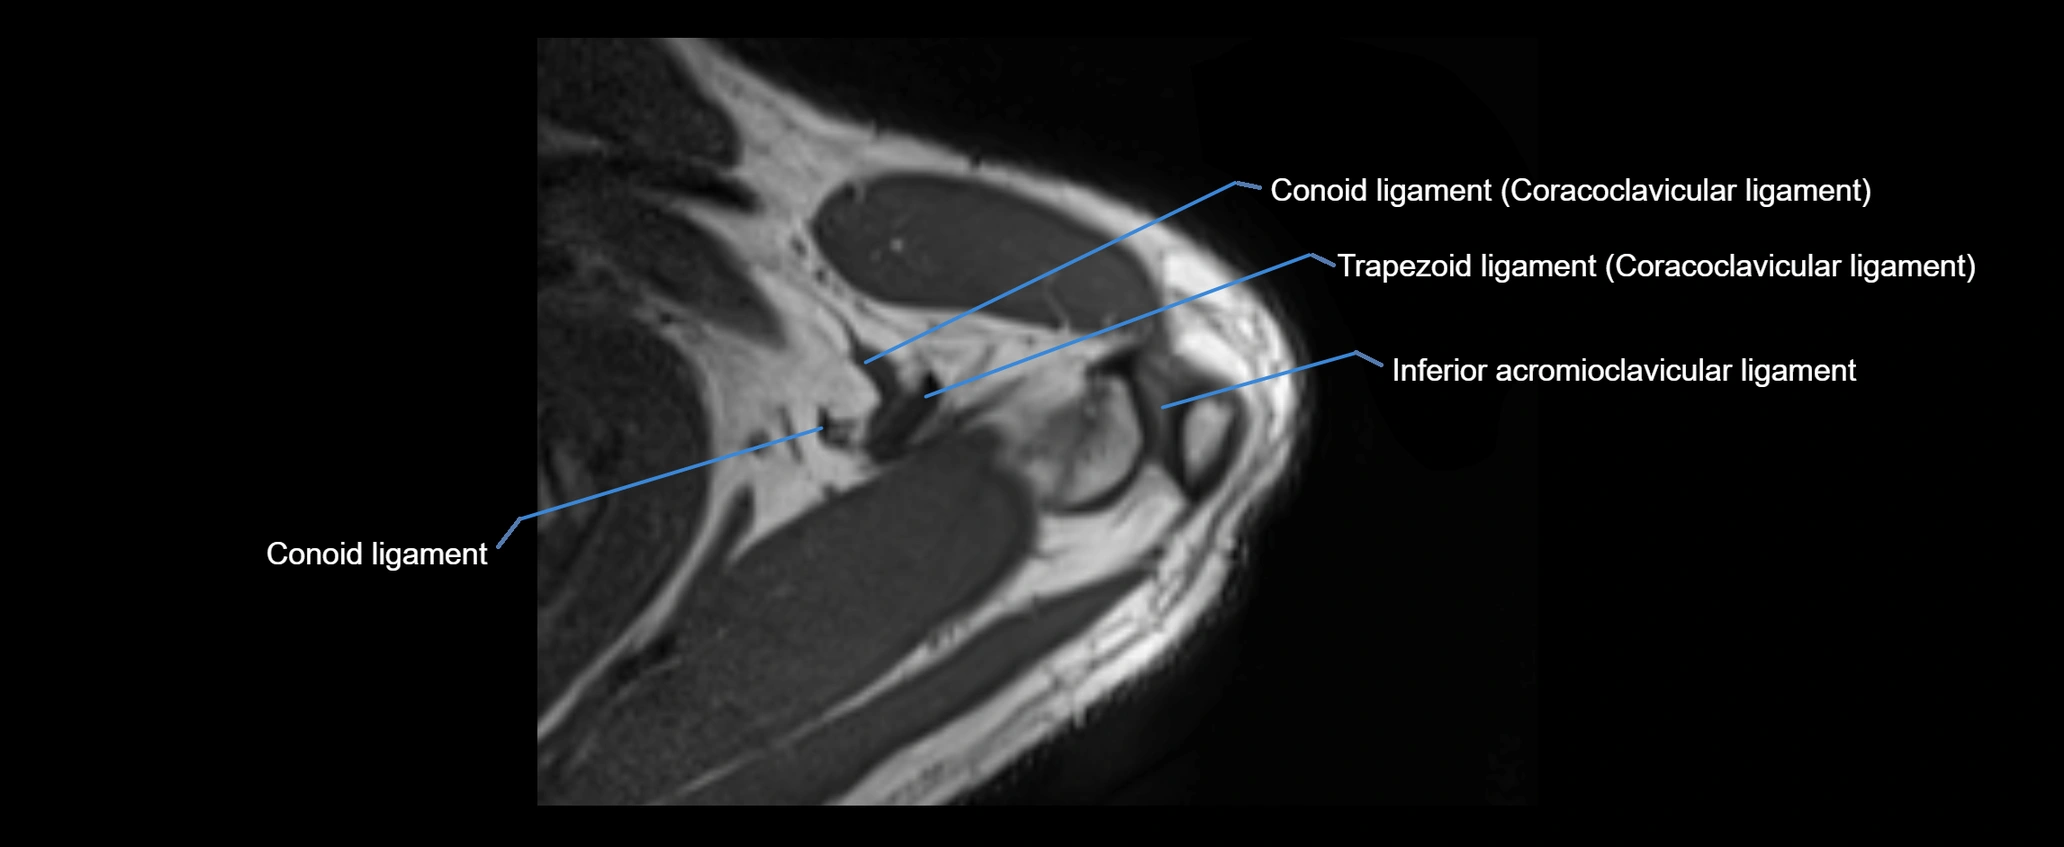

MRI images

image